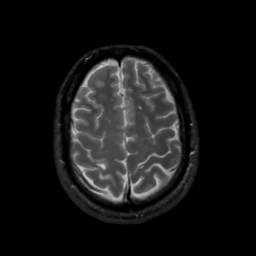

MR Study #16, June 23, 1991 -- Slice #40